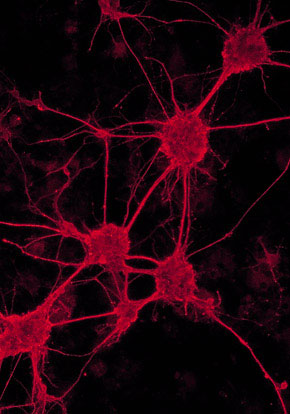

Here are some images of the neuron system in the brain

The differences between the brain from 1 month age till 1 year.